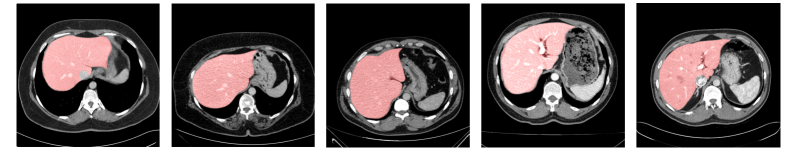

Figure 3 shows visual samples from the datasets used in our experiments: (a) FSS-1000, a natural image dataset illustrated with 10 example classes; and the medical datasets: (b) CHAOS-CT for liver segmentation, (c) Spleen-CT for spleen segmentation, (d) COVID-19 CT for lung infection segmentation, and (e) Cardiac MRI for left atrium segmentation. Segmentation masks are shown in green for FSS-1000 and in red for the medical datasets.

.